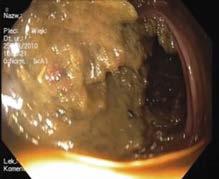

Endoskop należy wprowadzić do kątnicy, identyfikując ją poprzez uwidocznienie zbiegających się fałdów z ujściem wyrostka robaczkowego w miejscu ich połączenia oraz zastawki Bauhina. Zaleca się wprowadzenie endoskopu przez zastawkę do końcowego odcinka jelita krętego (ileokolonoskopia). Dokładnej oceny jelita dokonuje się w trakcie wycofywania endoskopu, co powinno trwać ≥6 min. Podczas badania należy ocenić przygotowanie jelita do badania za pomocą zwalidowanej skali, np. Boston (Boston Bowel Preparation Scale – BBPS). BBPS określa w punktach jakość przygotowania 3 segmentów jelita, ( kątnica-wstępnica, poprzecznica i zstępnica-esica), w skali 0–3 (ryc. III.B.4-31: 3 pkt – dobrze widoczna błona śluzowa, bez resztek kału i mętnego płynu; 2 pkt – błona śluzowa dobrze widoczna, w niewielkim stopniu pokryta grudkami kału i/ lub mętnym płynem; 1 pkt – błona śluzowa tylko częściowo widoczna z powodu dużej ilości stałego kału lub mętnego płynu; 0 pkt – jelito nieprzygotowane i błona śluzowa pokryta stałym, niedającym się spłukać kałem. Wynik stanowi suma punktów ze wszystkich segmentów jelita (np. BBPS 3+3+3/9). Za dobre przygotowanie uznaje się wynik ≥6 pkt dla całego jelita i ≥2 pkt dla każdego z segmentów. Podczas kolonoskopii należy wykonać dokumentację fotograficzną, obejmującą m.in. obszary pozwalające na ocenę głębokości wprowadzenia endoskopu (jelito kręte, zastawka krętniczo -kątnicza, dno kątnicy) i czasu jego wycofywania (odbytnica podczas wycofywania), oraz udo -

Ryc. III.B.4-31. Oczyszczenie jelita w skali

Boston: A – 0 pk t B – 1 pk t C – 2 pk t D – 3 pkt (fot. lek. Mateusz Szmit, dr Marek Bugajski, prof. Michał. F. Kamiński)